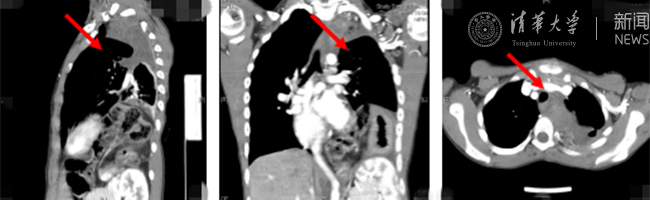

术后复查影像,患者体内的肿瘤已被切除。